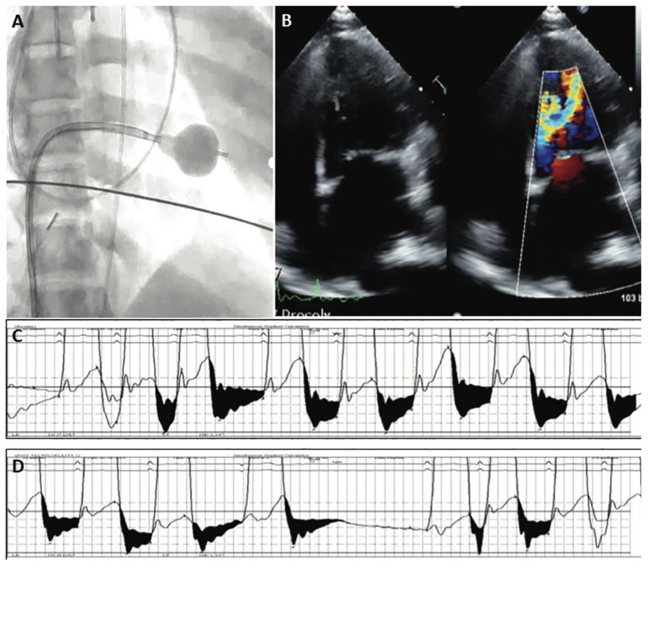

Percutaneous Mitral Valvuloplasty for Palliative Management of Severe Mitral Stenosis in a High-Risk Pregnancy

Ashleigh Long, MD, PhD; Deepak Talreja, MD, FACP, FACC, Sentara Heart Hospital, Norfolk, Virginia

The management of valvular heart disease in pregnancy is uniquely complex, requiring consideration of both maternal and fetal well-being within the context of the dynamic physiologic changes of pregnancy. As medical and surgical advancements allow more patients with acquired and congenital valvular disease to survive into their reproductive years, the number of patients with pregnancies complicated by valvular heart disease is likely to increase over time.

Though rheumatic mitral disease affects a smaller smaller percentage of patients from developed countries, it is the most common valvular disorder encountered during pregnancy on a global scale. Patients with rheumatic disease of the native mitral valve may have symptoms unmasked by the hemodynamic changes of pregnancy, causing missed pregestational diagnoses, and resulting in recurrent pregnancy loss, preterm delivery, and increased risk of maternal morbidity and mortality. In patients with severe mitral stenosis, the risk of decompensated heart failure without valvular intervention during pregnancy may be as high as 50%.